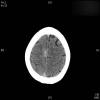

AVC amplio de territorio de A. cerebral media